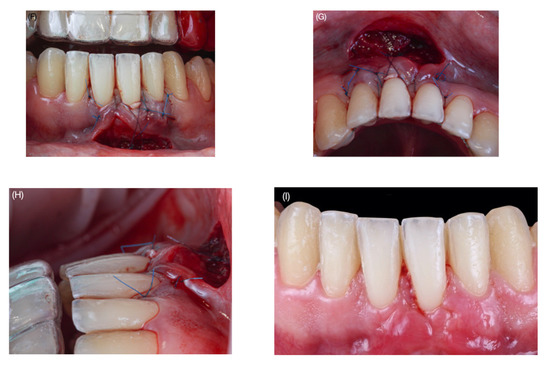

2.1. Surgical Protocol